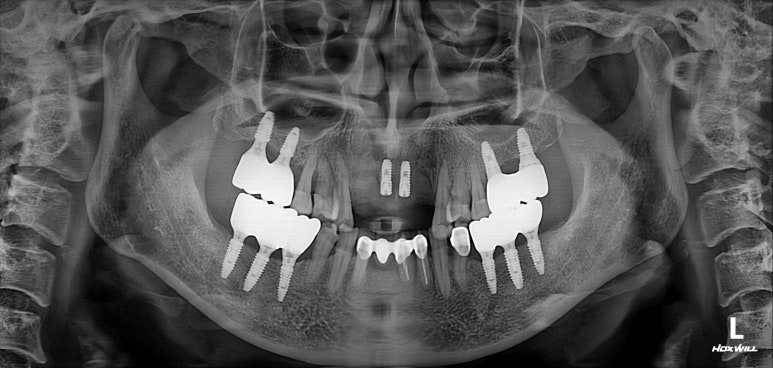

엑스레이를 보시면, 양쪽 위턱 가쪽 앞니가 거의 잇몸뼈와 분리되어 둥둥 떠있는 모습을 보실 수 있습니다.

잘 모르시겠다면, 제가 표시해드리겠습니다..!!

점선이 실제 잇몸뼈의 높이를 나타내고 있습니다.

노란 화살표로 표시한 두개의 위턱 측절치가 남아있는 뼈 없이 둥둥 떠있는 모양이에요.

axial view를 보시면, #12,22 부위에 정말로 엄청난 골소실이 있음을 보실 수 있을겁니다.

상악 전치부 보철은 양쪽 cantilever로 할 수 밖에 없는 상황이었습니다.